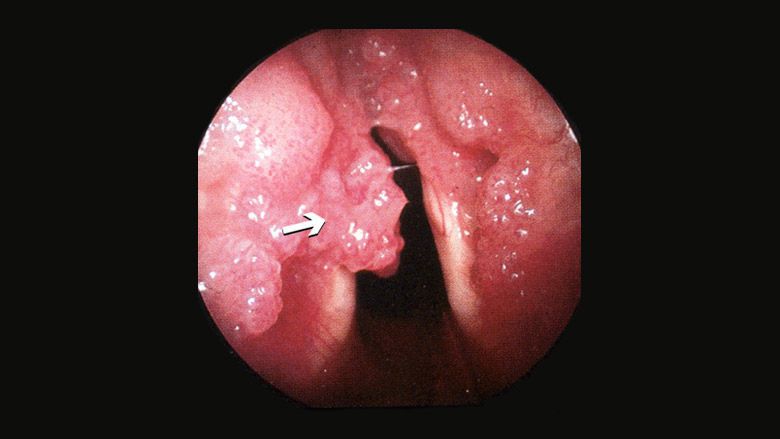

The most common symptoms of recurrent respiratory papillomatosis are: Chronic hoarseness. They include: Chronic cough. Episodes of choking. Recurrent pneumonia. Failure to thrive. Shortness of breath. Difficulty swallowing. Snoring.